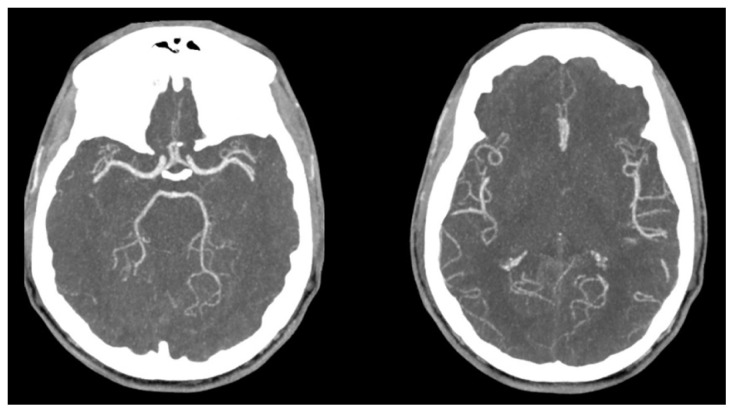

Acute Border Zone Infarcts in Hypereosinophilic Syndrome.